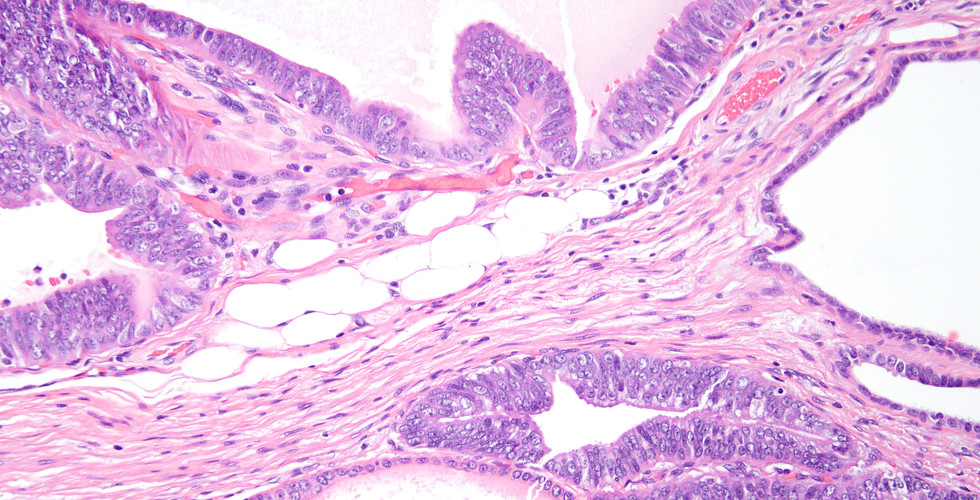

History: These images are from a radical prostatectomy specimen. What is your diagnosis?

Answer: PIN-like ductal adenocarcinoma extending far out of the prostate into periprostatic adipose tissue, negative for high molecular weight cytokeratin.

Comment: These tumors are variants of ductal adenocarcinoma since they have pseudostratified columnar cells and can co-mingle with usual papillary and cribriform ductal adenocarcinoma. Some authorities refer to them as PIN-like carcinoma since they have a similar prognosis to Gleason score 6 (Grade Group 1) acinar carcinoma (a better prognosis than historically considered ductal adenocarcinoma). This variant consists of simple, often cystically, dilated glands lined by pseudostratified columnar epithelium. The glandular lining is often flat, lacking the papillary or cribriform morphology initially described in ductal adenocarcinoma. As with other patterns of ductal adenocarcinoma, there can be a spectrum of cytological atypia, although typically PIN-like ductal adenocarcinoma lacks diffuse prominent nucleoli.